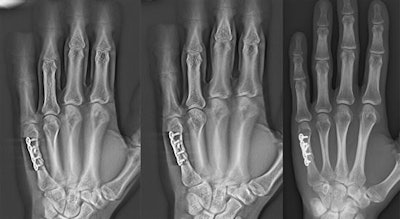

The proper installation of orthopedic hardware in the hand and wrist after surgery is usually confirmed with digital radiography (DR). But digital tomosynthesis (DTS) may further enhance visualization around such implants, according to research published online September 11 in Clinical Radiology.

A Swiss research team investigated the differences between using DR and DTS to image osteosynthesis material (OSM) after its surgical implantation into the hand and wrist of patients at University Hospital Zurich.

In light of this information, the researchers performed DR and digital tomosynthesis on the same hand or wrist of 35 patients with orthopedic implants. DTS was restricted to a -20° to 20° angle range and used to acquire 30 images of the region of interest in less than six seconds (Clinical Radiology, September 11, 2017).

Two radiologists independently evaluated the quality of each of the images, taking into account features such as the delineation of fracture outlines, positioning, and the appearance of metal artifacts.

Frauenfelder and colleagues found that DTS was significantly better at displaying the outline of fractures and highlighting the space between overlapping tissues, although the overall quality of DR and DTS images was about the same. Image quality was scored on a scale of 1 to 4, with 1 indicating excellent image quality.

While there was no statistically significant difference in overall image quality between DR and DTS, digital tomosynthesis does appear to have some advantages, according to the researchers.

"Based on the better results of DTS for delineation of bone structure, better complication detection is evident with DTS than with DR," they wrote.

Another important finding was that interobserver agreement between the two radiologists was markedly higher with DTS. The overall interobserver agreement was "excellent" for DTS (K = 0.96), while it was only "substantial" for DR (K = 0.77).

Despite enhancing the visualization of fracture margins and promoting interobserver agreement, DTS offered no more benefits than DR in terms of making diagnoses -- i.e., assessing osteosynthesis material after surgery. Both had the same scores of 1.03 for positioning and 1 for integrity of OSM. This finding was likely due to the appearance of more metal artifacts with DTS than DR, according to the researchers.